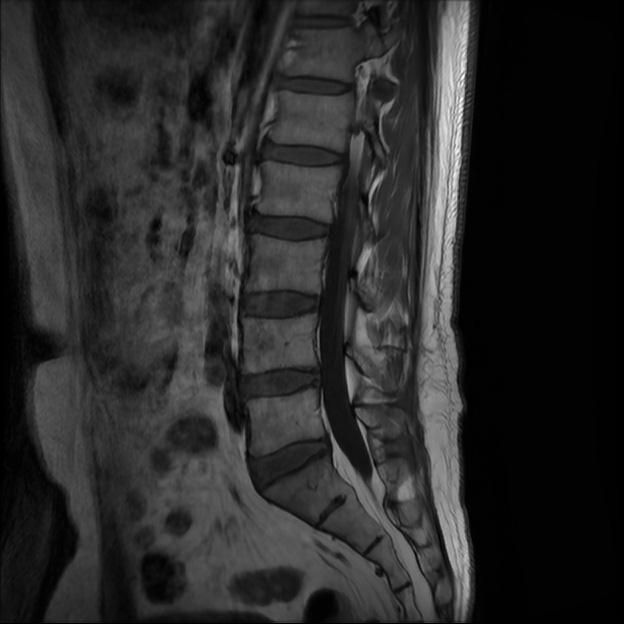

허리 MRI 전문가분들 의견부탁드립니다.

이번에 허리 MRI찍었는데

상태 어떤지 고견 여쭙습니다.

• 2번 째 사진

큰 이상이나 문제점은 없어 보이는 것으로 생각되는데요, 허리통증이 지속되는 경우에는 반드시 디스크 질환에 의한것은 아닐 수 있습니다.

현재로썬 디스크 상태는 심하지않는것으로 확인이 됩니다.